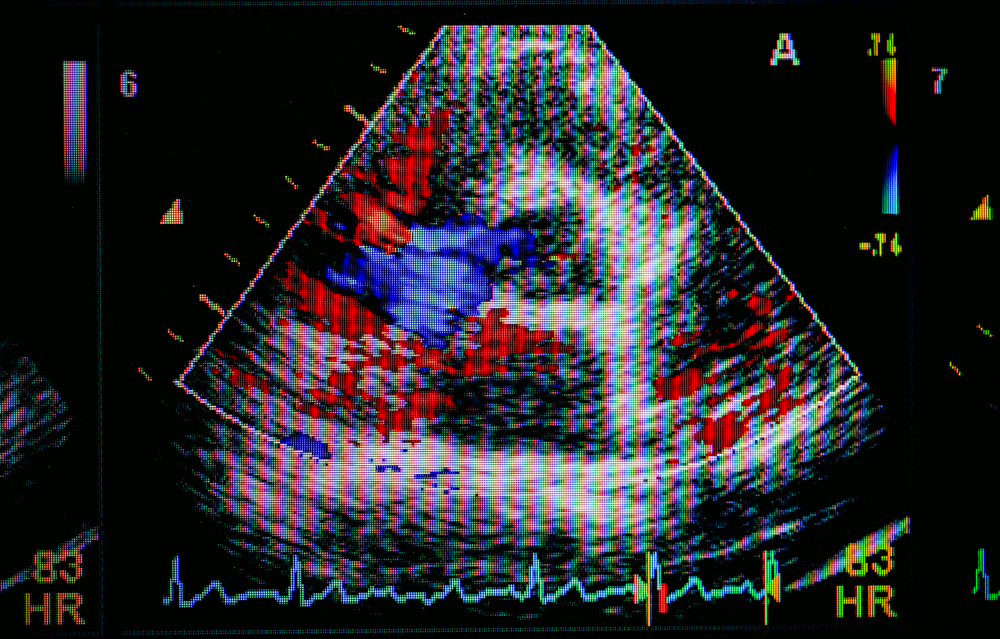

- Допплерэхокардиография. Проводится, как правило, параллельно с двухмерной эхокардиографией одним и тем же специалистом. При помощи данного метода врач наблюдает за током крови в предсердиях и желудочках, а также в крупных сосудах. В здоровом сердце движение крови всегда однонаправленно, но при патологии клапанов отмечается и обратный ток крови. Во время исследования ток крови выделяется на мониторе компьютера синим и красным цветом – в зависимости от его направленности. Кроме направления тока крови, во время проведения допплерографии врач оценивает, насколько выражен обратный кровоток (степень регургитации), определяет скорость прямого и обратного кровотока, а также измеряет диаметр отверстия, через которое проходит кровь. Данный вид исследования может проводиться самостоятельно, но чаще его используют в одном исследовании с М- и В-эхокардиографией.